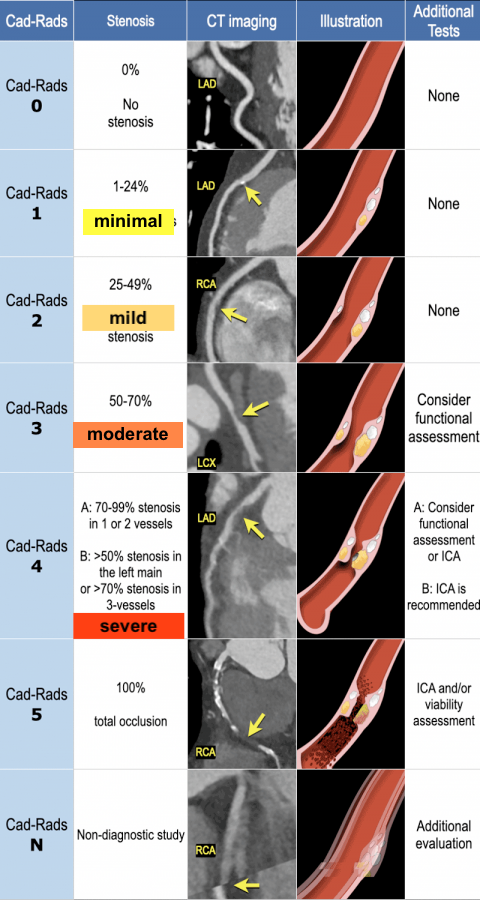

CAD-RADS

Sur segments de >2mm

Plaque Burden P(0-4) / HRP

- Le plus simple = par le CAC score Agatson,

- Inclure aussi les plaques à haut risques (HRP) chez les non calcifiées

- HRP = si deux signes de plaque à risque

- P3 et P4 = indication a ttt medicamenteux agressif (statines, anti plaquettaires)

- SIS = Segment involvment score (nombre de segments atteints)

Plaques à Risque

Remodellage positif

Core lipidique <30 HU

Napkin ring sign

Spotty calcifications

Modifiers “N”, “S”, “G”, “I” et “E”

- Modifier N Si Segment Non evaluable (typiquement artefact) et Sténose de >50% dans une autre coronaire

- Modifier S Si stent présent

- Modifier G Si bypass

- Modifier I Si ischémie

- Modifier E Autres anomalies (Dissection, Malformation, Vasculite, Anévrisme, Fistule, MAV, ETC)

Risque à 5 ans d’événement CV